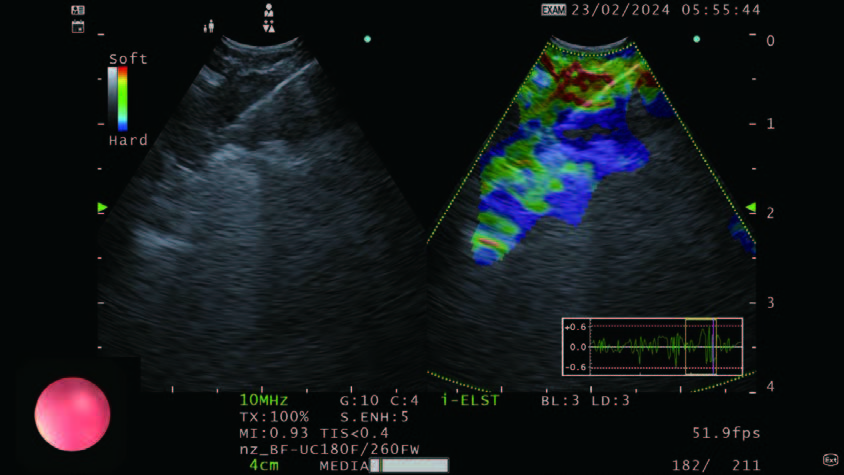

Figure 4 - The side-by-side B-mode and i-ELST allows us to target the appropriate areas within the lesion in real time.

Elastography is a recent addition that can assess the hardness of the lymph node during EBUS. There is a theoretical advantage when one can assess the nature of the node before sampling it and to decide whether sampling would be useful, and even better if there are different areas of the nodes that need to be sampled to improve the outcome of the puncture. While the previous version of this processor had this capability, the EU-ME3 is newly equipped with “i-ELST” mode, that enables stable ELST images even with weak pulsation. The option of being able to view a B-mode and Elastography or Doppler in the same frame as adjacent pictures (see Figure 4) helps us target the desired area of interest in the node.